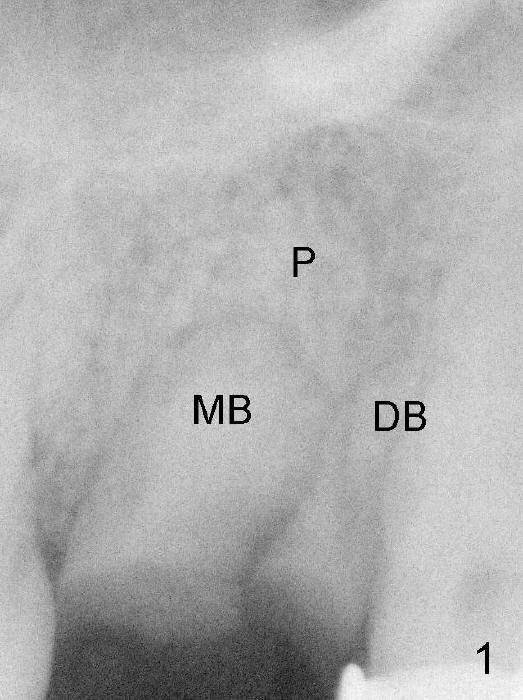

Fig.1: The upper left 2nd molar has 3 residual roots (MB, DB, P).